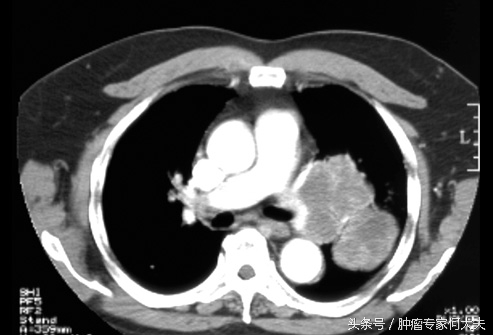

肺微浸润性腺癌能做消融手术吗,肺射频消融手术真实经历 消融技术是应用消融电极,在超声、CT引导下经皮肺穿刺,插入到肿瘤核心部位,通过射频输出,使病变区组织细胞离子震荡摩擦产生热量,局部温度达90℃以上,通过加热的温度来损害病变组织发生凝固性坏死,最终形成液化灶或纤维化组织,同时实时调节监控温度,从而达到局部消除肿瘤组织的目的,最后将穿刺针道加热消融,以防肿瘤种植。目前消融治疗大多在CT引导下完成,因为CT引导下射频消融,患者的治疗是在CT室完成的,不用进手术室,也不需要全身麻醉。